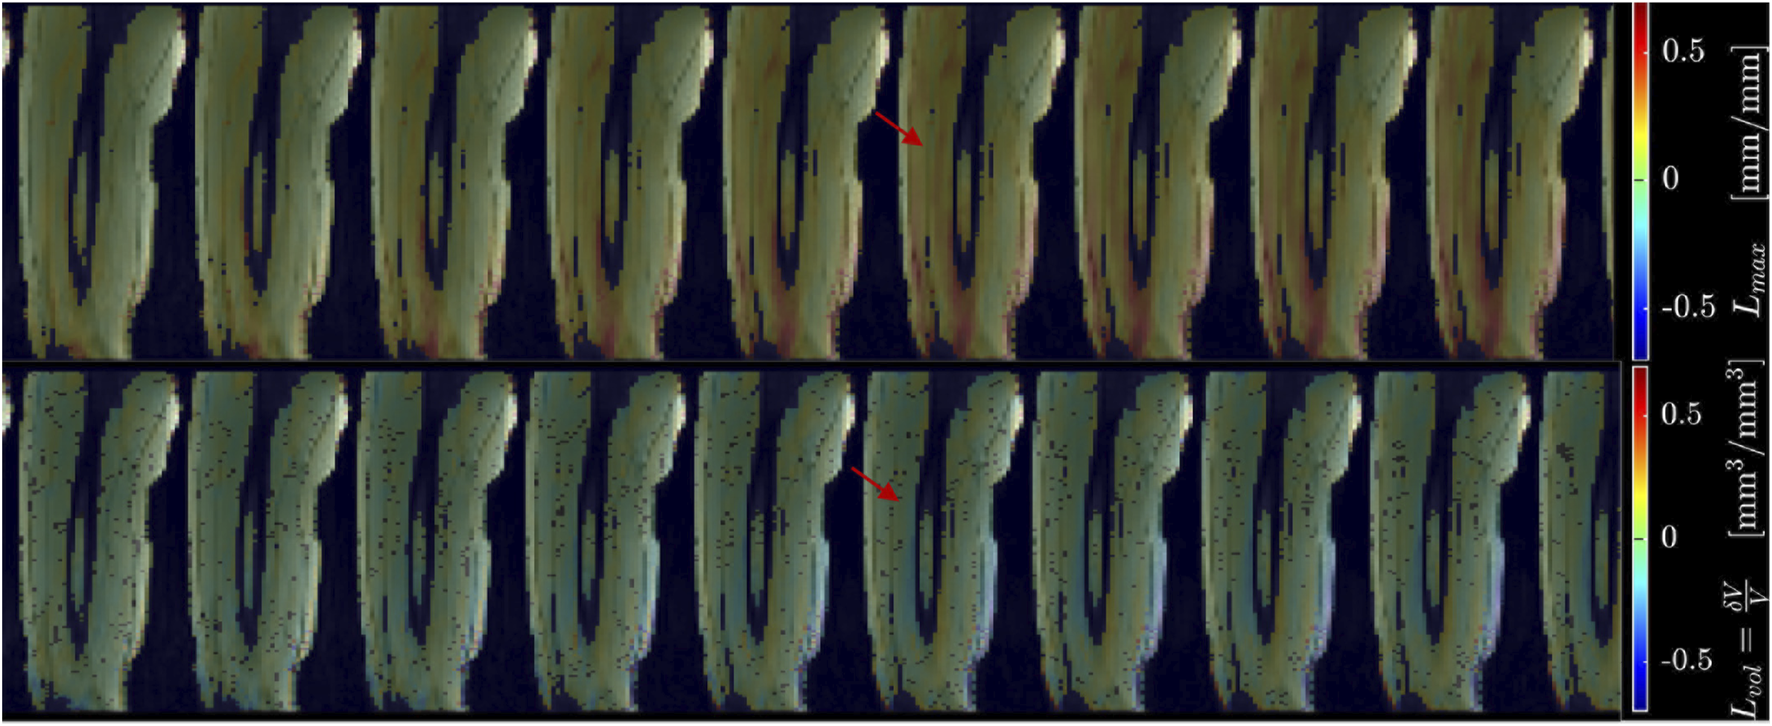

Figure 2 shows displacement maps (Δx, Δy, and Δz) of one slice (out of 24 slices in the volume) through 9 temporal frames (15-23 frames out of 32) of the isometric contraction cycle for one subject. The peak of the displacements occurs around frame 20, which is close to the peak of the force curve. The larger displacements in the x direction may arise from gross motion close to the knee region since the downward force exerted by the tibia causes the knee to rise. The large values of y-displacement along the aponeurosis between the RF and VI muscles are clearly evident near the peak of the force curve. Strain maps for the same subject are shown in Figure 3. The panels from top to bottom are the strain colormaps of Lλ1, Lλ2 and Lλ3 respectively for the same anatomical location and temporal frames as shown in the displacement maps. The larger values of the negative and positive strains in the quadriceps muscles (compared to hamstring muscles) and along the aponeuroses as well as the small strain values in the Lλ2 colormap can be readily visualized. The colormaps of the invariants Lmax and Lvol are shown in Figure 4 for the same anatomical slice and temporal frames as shown in Figures 2, 3. Visually, the maximum shear strain maps have the largest absolute values of the strain (compared to Lλ1, and Lλ3 colormaps) with larger values along the aponeuroses as in the Lλ1 and Lλ3 maps. The Lvol colormap shows low values as would be expected for an incompressible tissue like muscle since it is the relative change in volume. Supplementary Video S2 shows the strain maps through the dynamic cycle (Lλ1, Lλ2, Lλ3, and Lmax). Supplementary Video S3 shows the compressive strain through the dynamic cycle for select slices in the thigh volume. The spatial pattern of the compressive strain in the different thigh muscles can be seen as the volume is panned.

Figure 3. Colormaps of the strain eigenvalues: Lλ1 (top panel), Lλ2 (middle panel), Lλ3 (bottom panel). Lλ1 is the negative eigenvalue image while Lλ3 is the positive eigenvalue image. The second eigenvalue, Lλ2, is much smaller than the other two. One slice from the volume of 32 slices is shown here and the temporal frames span (from a total of 32) from 15 to 23 with the peak of the strain around frame 20 (red arrow) for isometric contraction at 30% MVC. The colormaps are superposed on the magnitude images at each temporal frame, the color-legend is shown on the right (negative: blue hues, positive: red hues).

Figure 4. Colormaps of the strain invariants: Lmax (top panel), Lvol (bottom panel). Lmax is the maximum shear strain while Lvol is the volumetric strain. The values of Lmax are higher than the absolute values of the normal strains. Lvol is small as would be expected for a nearly incompressible tissue like muscle. One slice from the volume of 32 slices is shown here and the temporal frames span (from a total of 32) from 15 to 23 with the peak of the strain around frame 20 (red arrow) for isometric contraction at 30% MVC. The colormaps are superposed on the magnitude images at each temporal frame, the color-legend is shown on the right (negative: blue hues, positive: red hues).